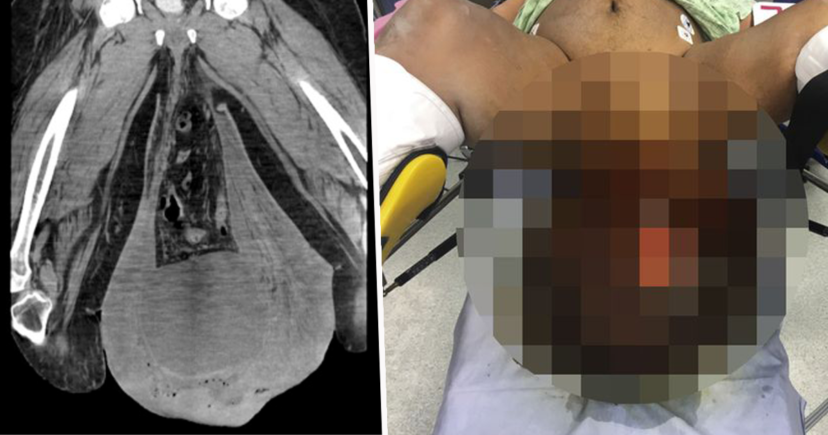

Après avoir fait passer une tomodensitométrie de l’abdomen, les médecins ont également découvert une hernie massive, ainsi qu’un gros abcès sous la peau, ce qui a aggravé encore plus sa situation. À cause de l’accumulation de l’urine, son rein s’est aussi enflé et sa peau était en train de pourrir.